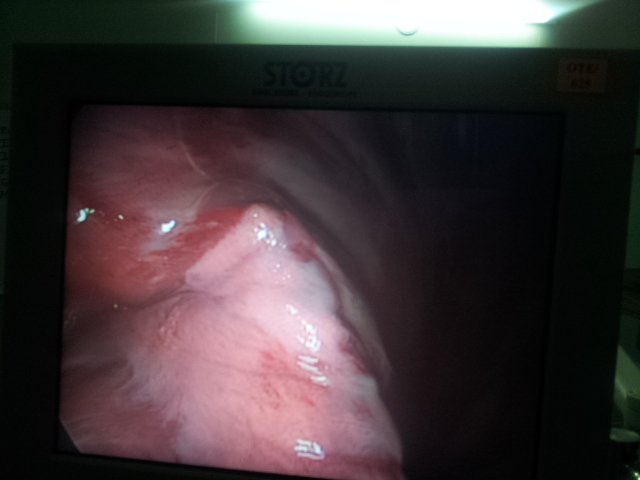

BEST CARDIAC SURGERY – VATS [THORACOSCOPY] & GENERAL THORACIC SURGERY

CARDIO THORACIC AND VASCULAR SURGERY